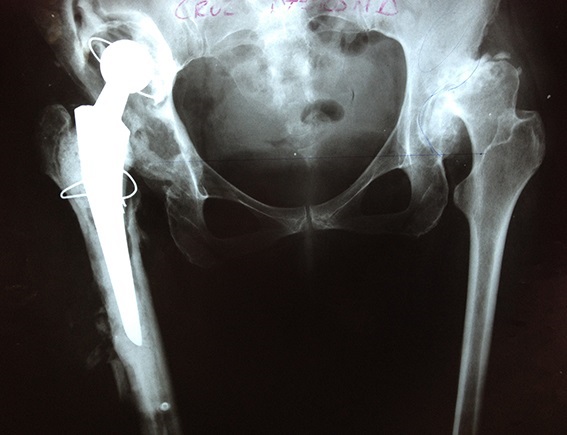

CORRECCIÓN DE AFLOJAMIENTO DE PRÓTESIS 1.PRÓTESIS AFLOJAMIENTO E INFECCIÓN DE VARIOS AÑOS. 2. RETIRO DE LA PRÓTESIS Y COLOCACIÓN DE PERLAS DE ANTIBIÓTICO ENTREVISTA PROGRAMA VIDA ENTREVISTA BDP CANAL 5 ENTREVISTA PIE PLANO ENTREVISTA ZAPATOS CORRECTOS INFILTRACIÓN DE ÁCIDO HYALURONICO EN CADERA